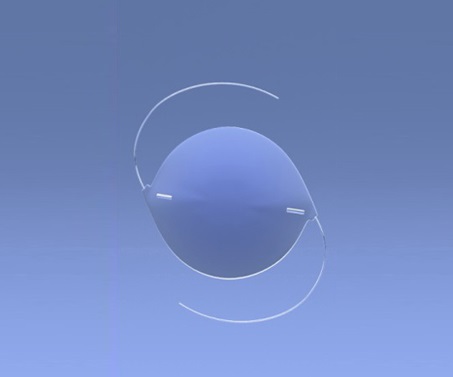

لماذا يعتبر زرع العدسة في جراحة ازالة المياه البيضاء ضرورة قصوى؟

أحادي البؤرة

فهو يوفر رؤية واضحة على مسافة واحدة، وعادة ما تكون بعيدة.

توريك IOL

إنه يُصحح الاستجماتيزم، ويُحسّن جودة رؤيتك.

Multi-focal IOL

فهو يصحح الرؤية على مسافات مختلفة، بما في ذلك الرؤية القريبة والمتوسطة والبعيدة.